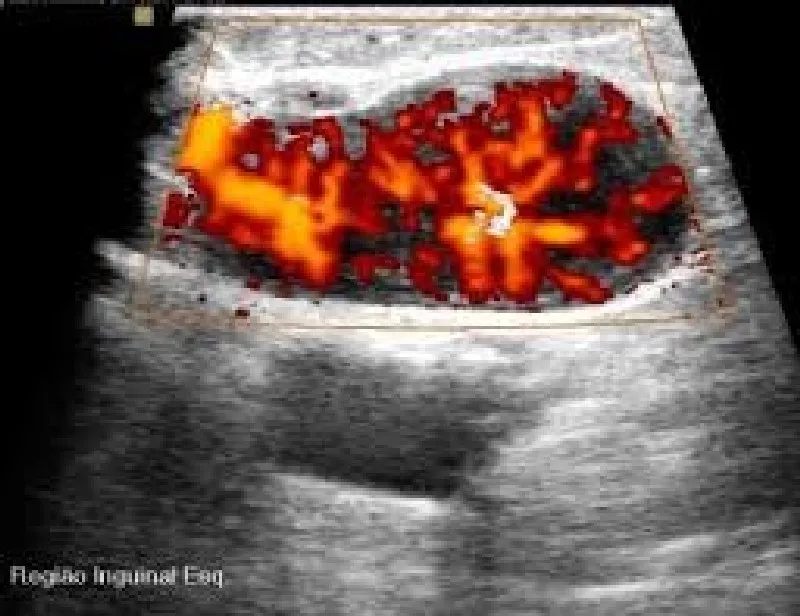

Com a possibilidade de ser alugada com uma empresa de outsourcing de impressão de alta confiabilidade, a impressora de ultrassom proporciona que as imagens deste exame, formadas por meio das ondas sonoras emitidas e captadas durante o processo, sejam impressas em alta qualidade no papel fotográfico, eliminando a necessidade de impressão em filme dry. O processo realizado com a impressora de ultrassom é veloz e permite que o profissional de medicina altere as imagens do exame antes da impressão, melhorando elementos como cor e contraste. Todos estes fatores contribuem para um diagnóstico mais rápido e preciso, o que beneficia o paciente e otimiza o tratamento.